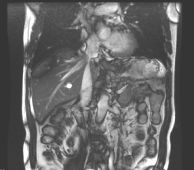

(2022.07.13)MR:1.右肝多发结节,考虑转移瘤可能,较前缩小2.左肾占位,错构瘤可能,MT待排3.双肾多发囊肿4、降结肠壁增厚,考虑MT。

image.pngimage.png